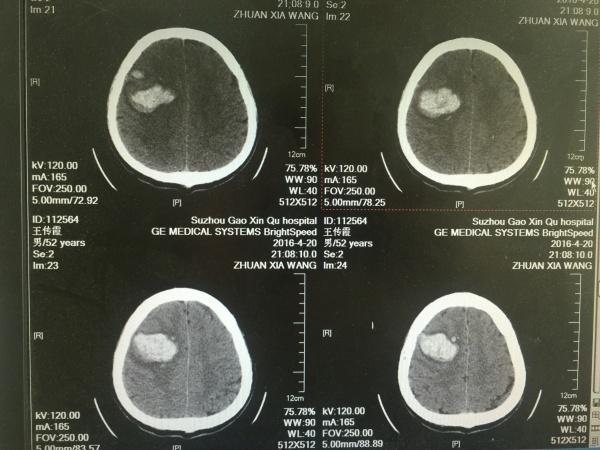

患者中年,女性,既往无高血压病史,此次因突发意识障碍1小时余入院,***血压230/123mmHg,神志呈昏睡,舌后坠,予以口咽通气道置入,急诊CT如下图,今日入院后第二日,复查颅内出血未见明显增加,因非高血压性脑出血常见部位,故行头颅CTA检查未见AVM及动脉瘤等血管病影像,病情现继观。